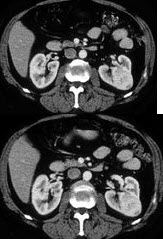

女,47岁,左侧腰部隐痛不适2个月余,结合所示图像最可能的诊断为()

A .左肾癌

B .左肾血管平滑肌脂肪瘤

C .左肾出血性囊肿

D .左肾炎性包块

E .左肾感染性囊肿